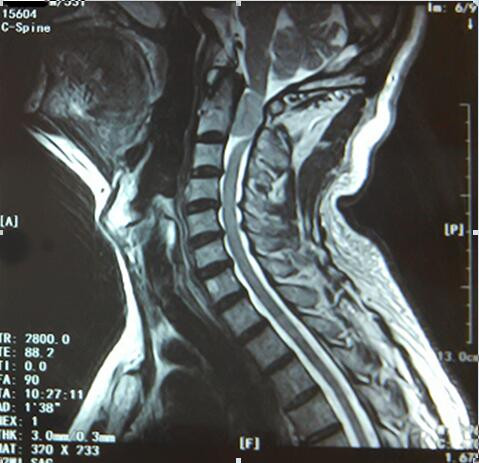

李先生53岁,入院前两个月出现肢体麻木、无力的症状,在个人诊所行针灸、按摩等治疗后症状略缓解。入院前一周,李先生肢体麻木、无力的症状加重,且行走不稳,李先生及家人这才意识到问题严重,想到北京或哈尔滨等大医院就医,但是由于经济方面的原因不能实现,于是多方打听后方知我院可以做这方面的手术,便立即来我院寻求救治。经MRI检查显示:“C2水平椎管内占位性病变”。白玉江主任团队经过反复术前讨论后决定为李先生行后路椎板切开减压、硬膜切开、肿物切除术。手术过程非常顺利。术后病理检查回报:(椎管内)脑膜瘤。每一个月随访至六个月,李先生恢复良好,无复发。

手术难度:该肿瘤已占椎管的90%,严重压迫脊髓,影响患者肢体感觉及运动,若肿瘤继续生长持续压迫脊髓,因病变节段高,可导致膈肌运动消失,以致呼吸衰竭,危及患者生命。手术风险极大,术中操作需格外谨慎,若强行切除肿瘤损伤脊髓,患者有呼吸停止的可能;此外因脊髓长期持续受压迫,一旦解除压迫,还需防止脊髓再灌注损伤的可能,若发生再灌注损伤则导致患者呼吸停止、死亡。

术前颈椎MRI